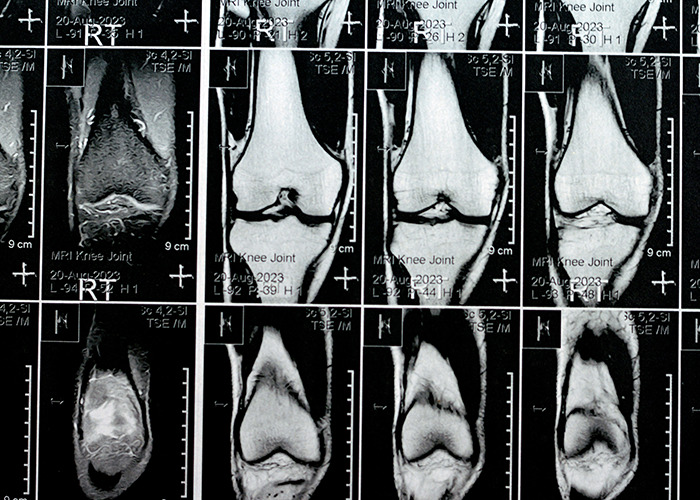

Image credits: Pixel_B/Adobe Stock (Not the actual photo)

“Although osteometabolic diseases are relatively well understood, there’s a gap in our knowledge regarding the influence of microplastics on the development of these diseases,” researcher Rodrigo Bueno de Oliveira explained in the original report.

The review noted that microplastics “were recently detected in human bone tissue,” and that in laboratory settings, they affected cell viability, gene expression, and inflammatory responses, all processes crucial to bone health, according to Yahoo News.

Because bone marrow produces red and white blood cells, even small disruptions could carry big consequences. As the researchers wrote, experimental animal studies showed that microplastics ingestion “disturbs gut microbiota and reduces white blood cell counts, suggesting compromised bone marrow function.”